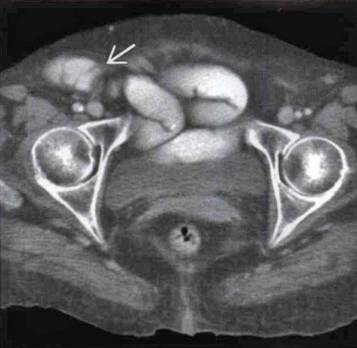

闭孔疝ct表现图

病例分享:闭孔疝典型ct表现,不要错过了!